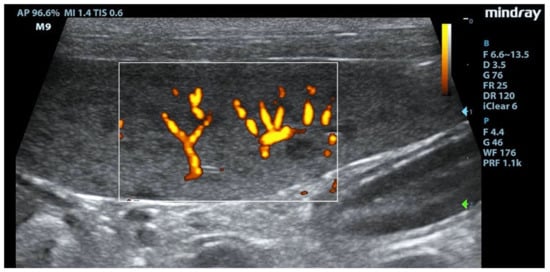

3.2. B-Mode Ultrasonography

Splenic enlargement was found in 11/22 (50%) leishmaniotic patients. Overall, 7/11 (63.6%) had diffuse parenchyma abnormalities, which were always accompanied by an increased size (Figure 1). Parenchyma had a moth-eaten appearance in 4/7 and a marbled appearance in 3/7. In the remaining four, spleen was subjectively reported to be of a larger size than normal but with a normal echotexture. A positive correlation with the clinical stage of disease was detected for splenic enlargement (r = 0.634; p = 0.036) and diffuse parenchymal alterations (r = 0.655; p = 0.047). The correlation between ultrasonographic alteration and splenic quantitative PCR showed a low positive effect (r = 0.06; p = 0.779). Conversely, there was no correlation between spleen enlargement and echotexture with lymph node parasite load (r = 0.26; p = 0.573, r = −0.329; p = 0.4705, respectively) and IFAT title (r = 0.33, p = 0.1413, r = −0.38; p = 0.09, respectively). In none of the three dogs negative for L. infantum were splenic enlargement or abnormalities of echotexture detected. Upon CPD examination, flow signals were detected in both normal appearance and in moth-eaten and marbled spleens; under careful observation, CPD frames in moth-eaten spleens showed the absence of flow in the more visible hypoechoic foci (Figure 2).

Figure 2.

Absence of signal at Color Power Doppler (CPD) in hypoechoic areas of the moth-eaten pattern of the spleen. F: probe’s frequencies; D: distance; G: gain; FR: frame rate; DR: dynamic range; AP: acoustic power; MI: mechanichal index; TIS: tissue imaging specific; M9: ultrasound system. Blue and green arrows: focal points.

CPD examination and CEUS were used to study splenic microvascularization. After the inoculation of the contrast agent, normal splenic parenchyma showed the rapid enhancement of the small splenic arteries, a heterogeneous phase of enhancement that became homogeneous at the end of the wash-in phase, and a slow wash-out [39]. Though the contrast medium did not have a late tissue phase in the dog’s spleen, the slow decay of enhancement would have been related to the accumulation in the sinusoids network [40]. A CPD examination showed no flow signal from small hypoechoic areas in the moth-eaten pattern of the spleens. In moth-eaten spleens, CEUS was used for the first time and showed, through a persistence of diffuse inhomogeneity with areas of hypoenhancement or absence of enhancement, that the alterations found in the B-mode images also led to a modification of the vascular architecture throughout the organ. A similar heterogeneous appearance and a widespread hypoenhancement were also found in the marbled spleens. Spleen microvascular architecture changes emerged in L. infantum-positive dogs from an ultrastructural study independently of their antibody titers. A marked scarcity of the sinusoidal system sheet that surrounds the central artery/arteriole of the white pulp, a huge development of pulp venules and veins, and the presence of a development of reticular fibers were reported [13]. Interestingly, we evidenced that an abnormal pattern of enhancement was only in spleens with B-mode ultrasonography alterations, and we can only speculate about these results. This in vivo study of vascular architecture obtained with CEUS was, however, not able to highlight changes in the splenic vascular pattern in all infected dogs other than what was reported with ultrastructural evaluation [13]. The statistical analysis of the CEUS quantitative parameters, relating to the speed and volume of splenic blood flow, did not show statistically significant differences in the examined ROIs. This was probably due to the inhomogeneity of splenic enhancement in leishmaniotic subjects that was not quantitatively detectable through the pixel analysis of different areas, even when comparing relatively small ROIs, because of the widespread alteration of the splenic vascularity of parenchyma. Substantial evidence supports that the spleen plays a key role in the immunopathology of VBP infections [41,42]. Splenomegaly might be due to a multiplication of organisms within circulating mononuclear cells and mononuclear phagocytic tissues of spleen and lymph nodes. Splenomegaly is a result of reactive lymphoid hyperplasia and concurrent extramedullary hematopoiesis [43]. In canine babesiosis and ehrlichiosis, the most common splenic ultrasonographic findings have been a diffuse heterogeneous hypoechoic pattern and generalized splenomegaly [44,45]. CEUS exams were performed in the spleens of dogs with subclinical ehrlichiosis, and a higher velocity of blood flow (lower wash-in time, peak enhancement time, and wash-out time) compared to data from healthy dogs examined in previous studies was seen [45]. In our study, molecular investigations of blood samples and splenic aspirates showed them to be negative for R. conorii, B. canis, E. canis, A. phagocytophilum, A. platys, and C. burnetii, so we can consider it unlikely that the ultrasound changes of the spleen could be traced to other VBP coinfections with L. infantum.